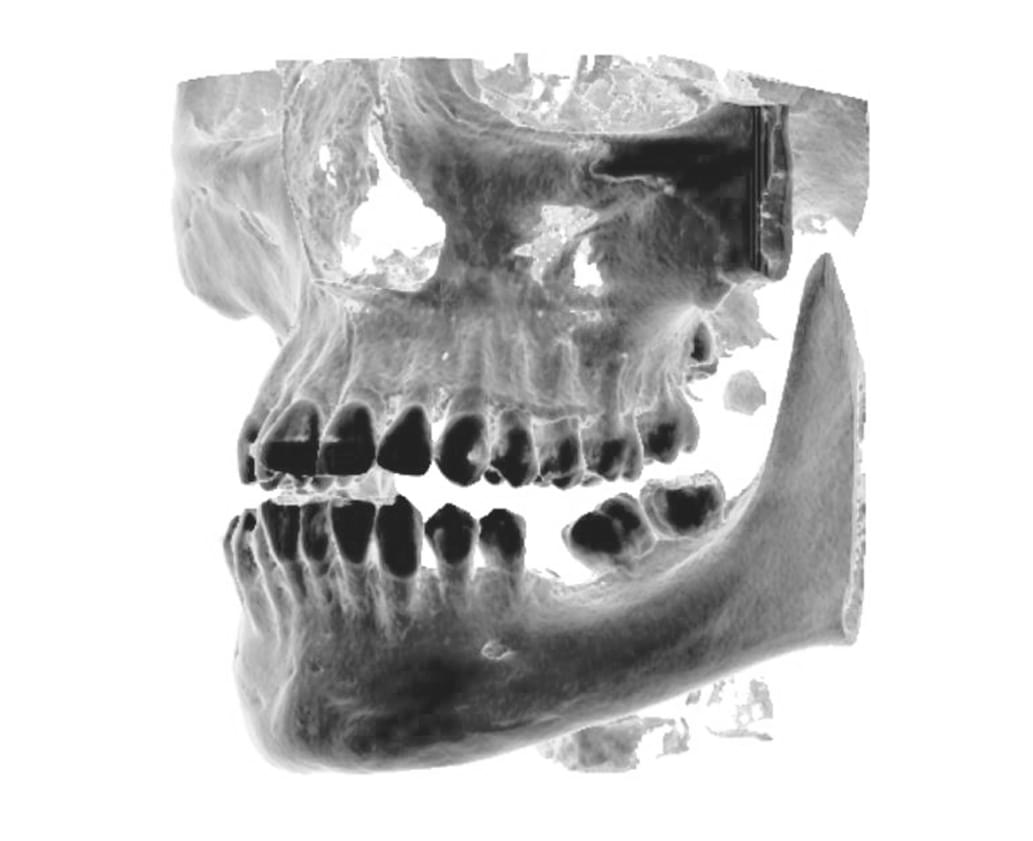

Výpočetní tomografie

(3d čelisťové snímky a snímky ústní dutiny)

CBCT Maxilofaciální diagnostika

Využíváme nejmodernější zařízení